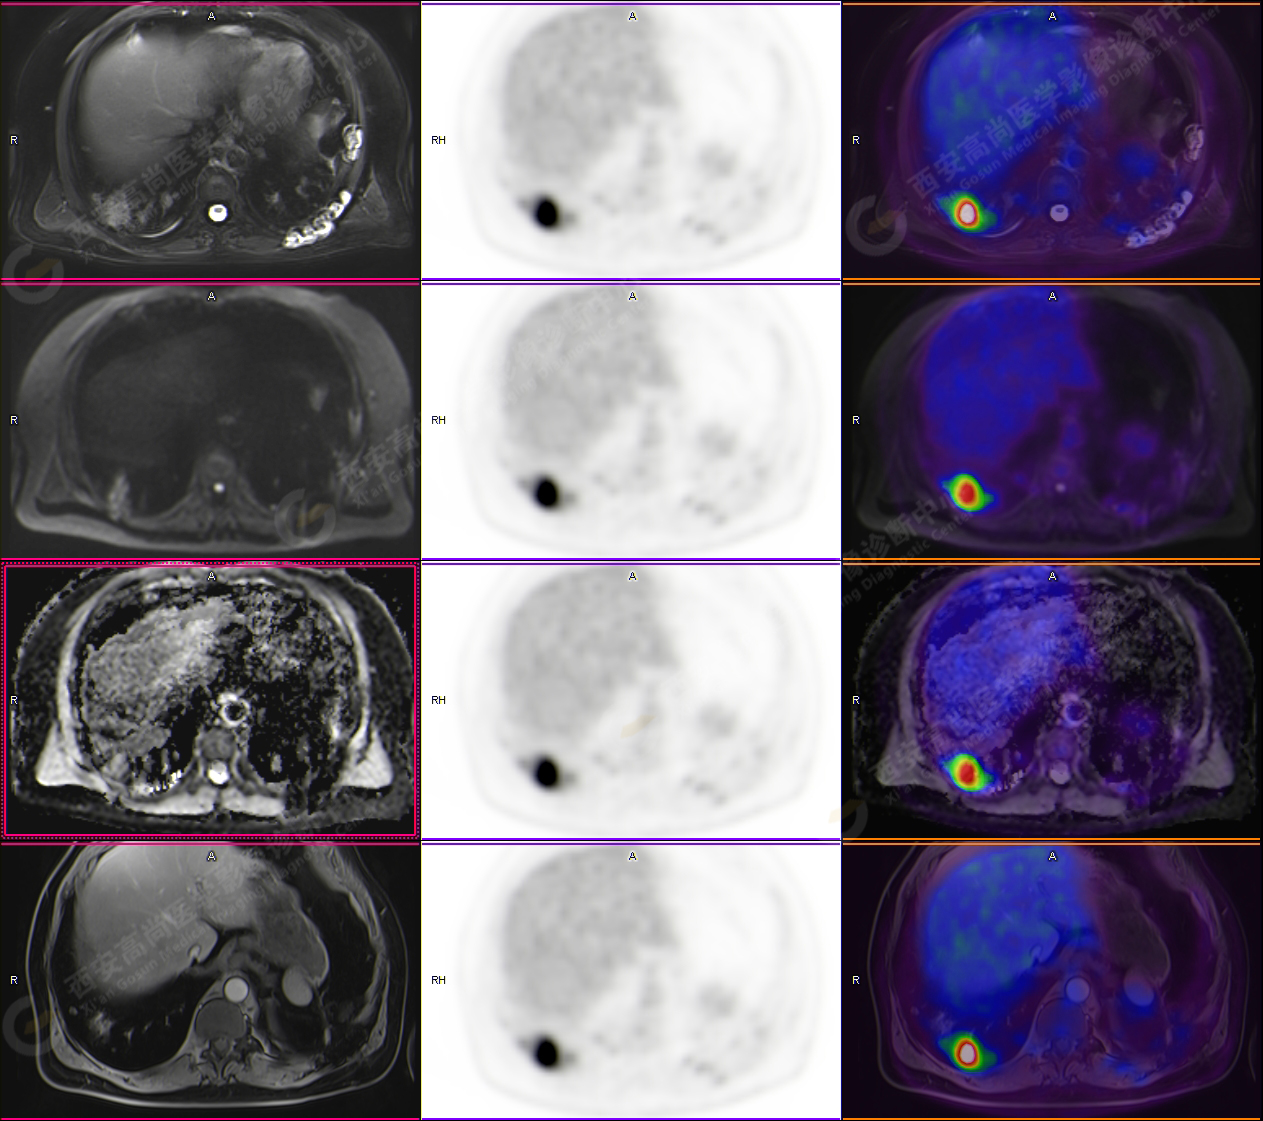

PET/CT圖像